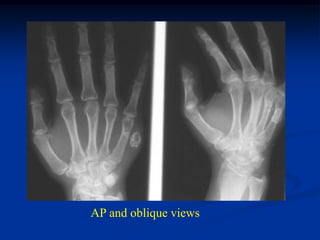

Case #293

X-ray showing calcifying mass

AP and oblique views

Surgical removal

Photomic showing cavernous vascular spaces